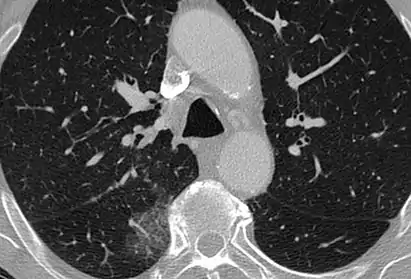

CT image showing centrilobular pattern of GGOs in patient with pulmonary tuberculosis. Note the small, nodular areas of increased attenuation in both lungs.

Centrilobular GGOs refer to opacities occurring within one or multiple secondary lobules of the lung, which consist of a respiratory bronchiole, small pulmonary artery, and the surrounding tissue.[3] A defining feature of these GGOs is the lack of involvement of the interlobular septum. Potential causes of centrilobular GGOs include pulmonary calcifications from metastatic disease, some types of idiopathic interstitial pneumonias, hypersensitivity pneumonitis, aspiration pneumonitis, cholesterol granulomas, and pulmonary capillary hemangiomastosis.[6]